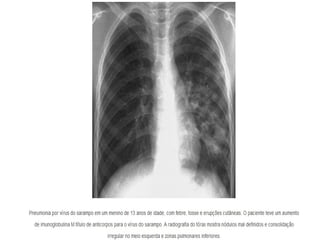

Crianças deficientes em células T que foram

infectadas com o sarampo produzem de forma atípica

uma pneumonia por células gigantes sem exantema.

Sarampo •A imunidadecelular é responsável pela maioria dos sintomas, mas também é essencial no controle da infecção do sarampo. Crianças deficientes em células T que foram infectadas com o sarampo produzem de forma atípica uma pneumonia por células gigantes sem exantema.